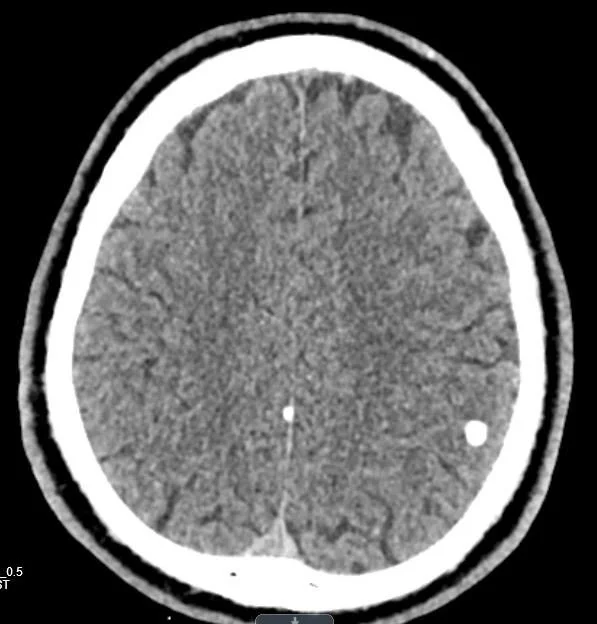

Our patient has a low grade tumor with significant potential to obstruct the airway. Surgery is planned. He was incidentally discovered to have calcifications in the brain. Presumably this is from an old parasitic infection. Neurocysticercosis is the most frequent parasitic infection of the nervous system and has been reported in the West Indies.